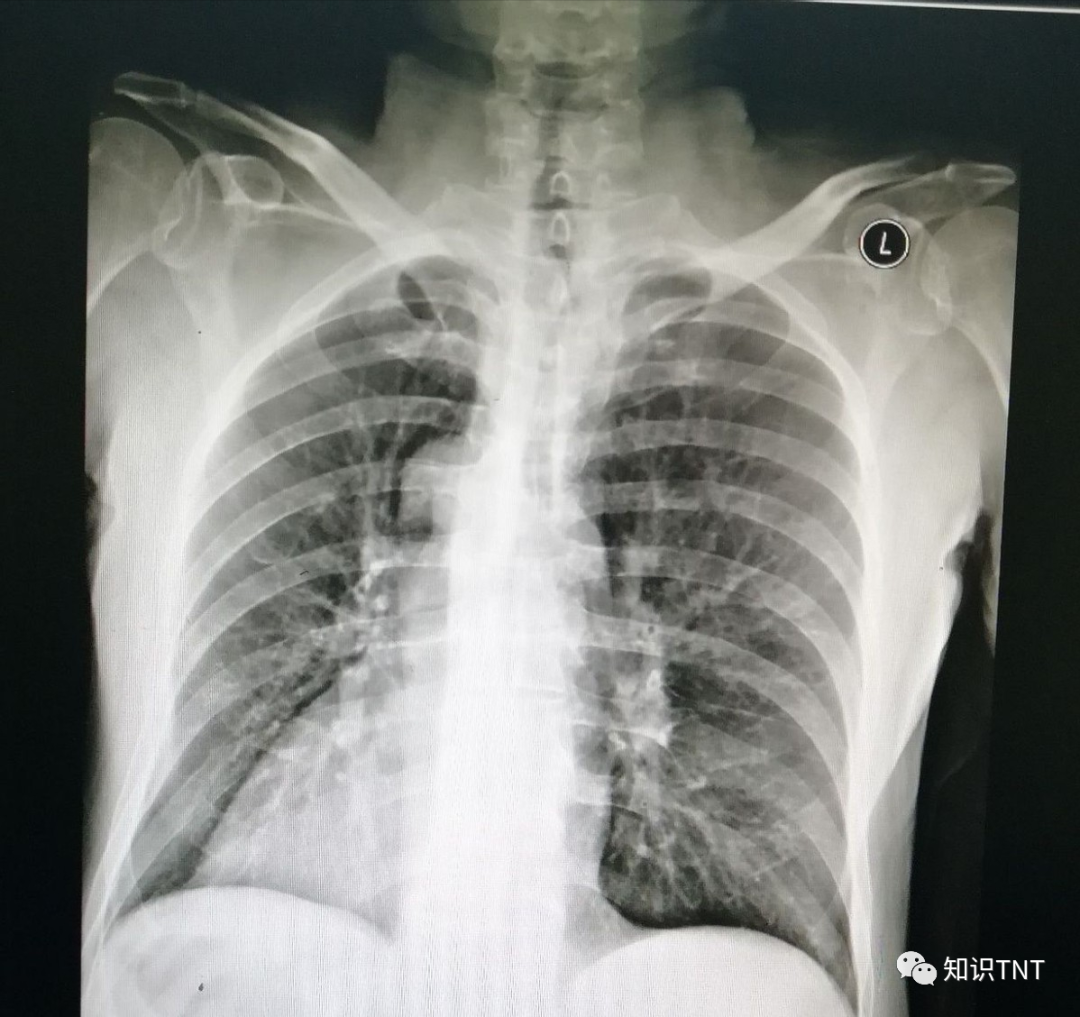

当然也不排除还有另一种特殊用途就是,如果是因为比较罕见的疾病导致的截肢,手术后的废肢一般都不会交还给患者,因为医院还需要这些组织来对疾病进一步的诊断,这些组织都会送到医院的病理科进行病理组织活检。

而当病理科的医生对这些手术中切下来的组织检查完之外,用福尔马林液泡起来作为标本制作,其他剩下的残肢部分组织按照医疗废弃物来处理掉,由专门的人员进行无害化处理。